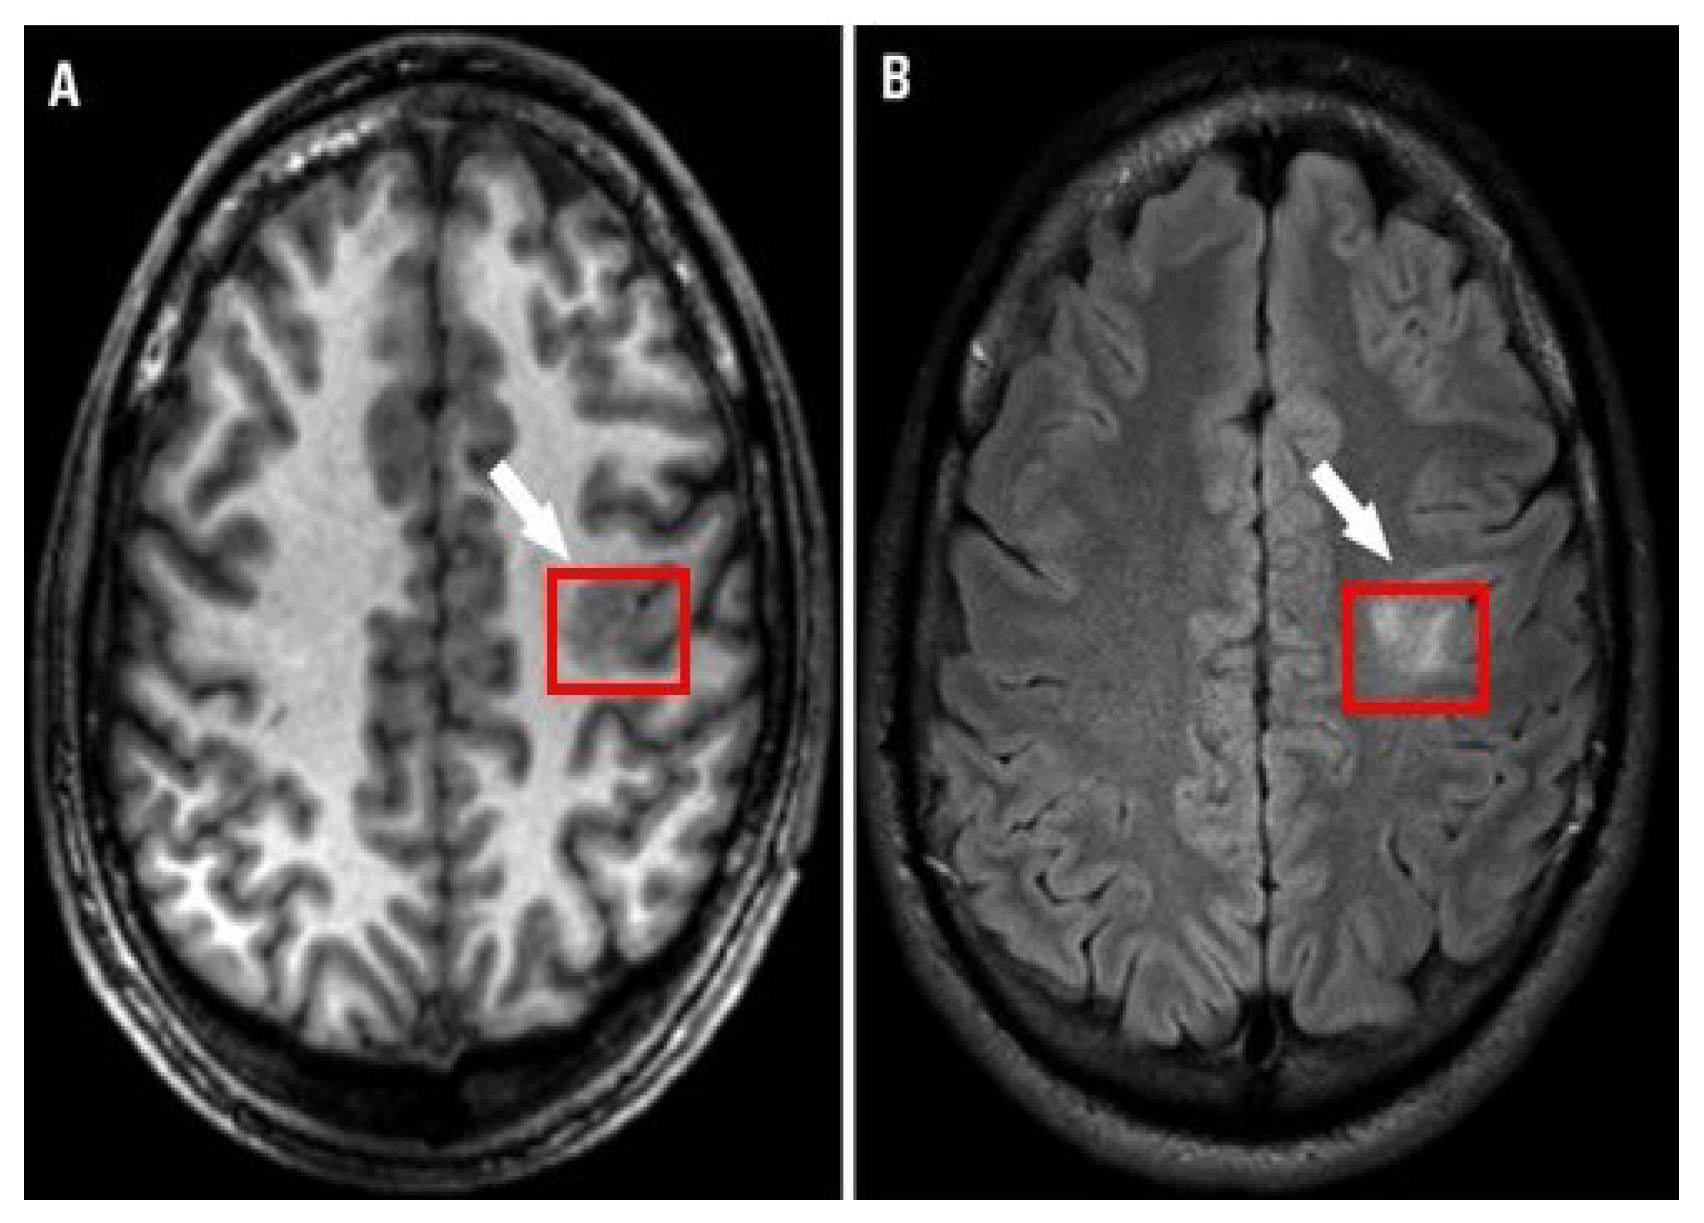

Figure 1.

Focal cortical dysplasia lesion (A) T1-weighted MRI and (B) FLAIR MRI [10].